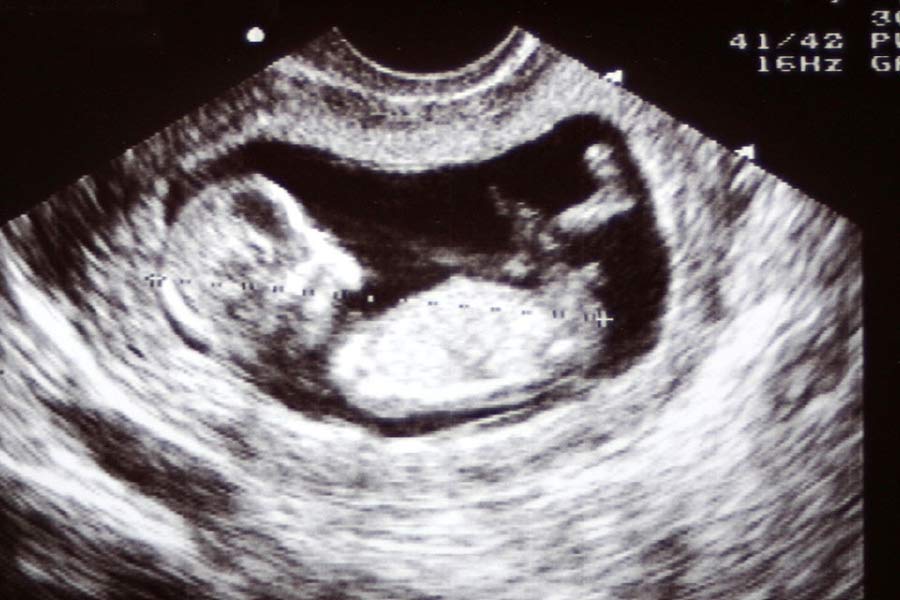

এ দিকে ছয় মাসের ভ্রূণ নাবালিকার গর্ভে। অগস্ট মাসে যখন ধর্ষণের কথা প্রকাশ্যে আসে তখন ইতিমধ্যেই সে ১৮ সপ্তাহের অন্তঃসত্ত্বা। চিকিৎসকদের কাছে গর্ভপাতের অনুরোধ জানিয়ে নাবালিকাকে কৌশাম্বী হাসপাতালে ভর্তি করেন তার বাবা।

যখন হাসপাতালে ভর্তি করানো হয় তখন সে ২৪ সপ্তাহের অন্তঃসত্ত্বা। ডাক্তারদের কাছে গর্ভপাতের অনুরোধ করলেও তাঁরা রাজি হননি।

নাবালিকার গর্ভের ভ্রূণ তখন ২৯ সপ্তাহে। নির্যাতিতার বাবার আর্জি শুনে ১৫ অক্টোবর কৌশাম্বী জেলা হাসপাতালের প্রধান মেডিক্যাল অফিসার সুষ্পেন্দ্র কুমারকে ডেকে ডাক্তারদের একটি মেডিক্যাল দল গঠন করার নির্দেশ দেয় আদালত।

প্রধান মেডিক্যাল অফিসার ২ নভেম্বর আদালতকে জানান, ওই নাবালিকা বর্তমানে ৩১ সপ্তাহের অন্তঃসত্ত্বা। সহজ পদ্ধতিতে গর্ভপাতের সময় পেরিয়েছে। এখন গর্ভপাত করতে অনেক সমস্যা। সেই পরিকাঠামো কৌশাম্বী জেলা হাসপাতালে নেই।